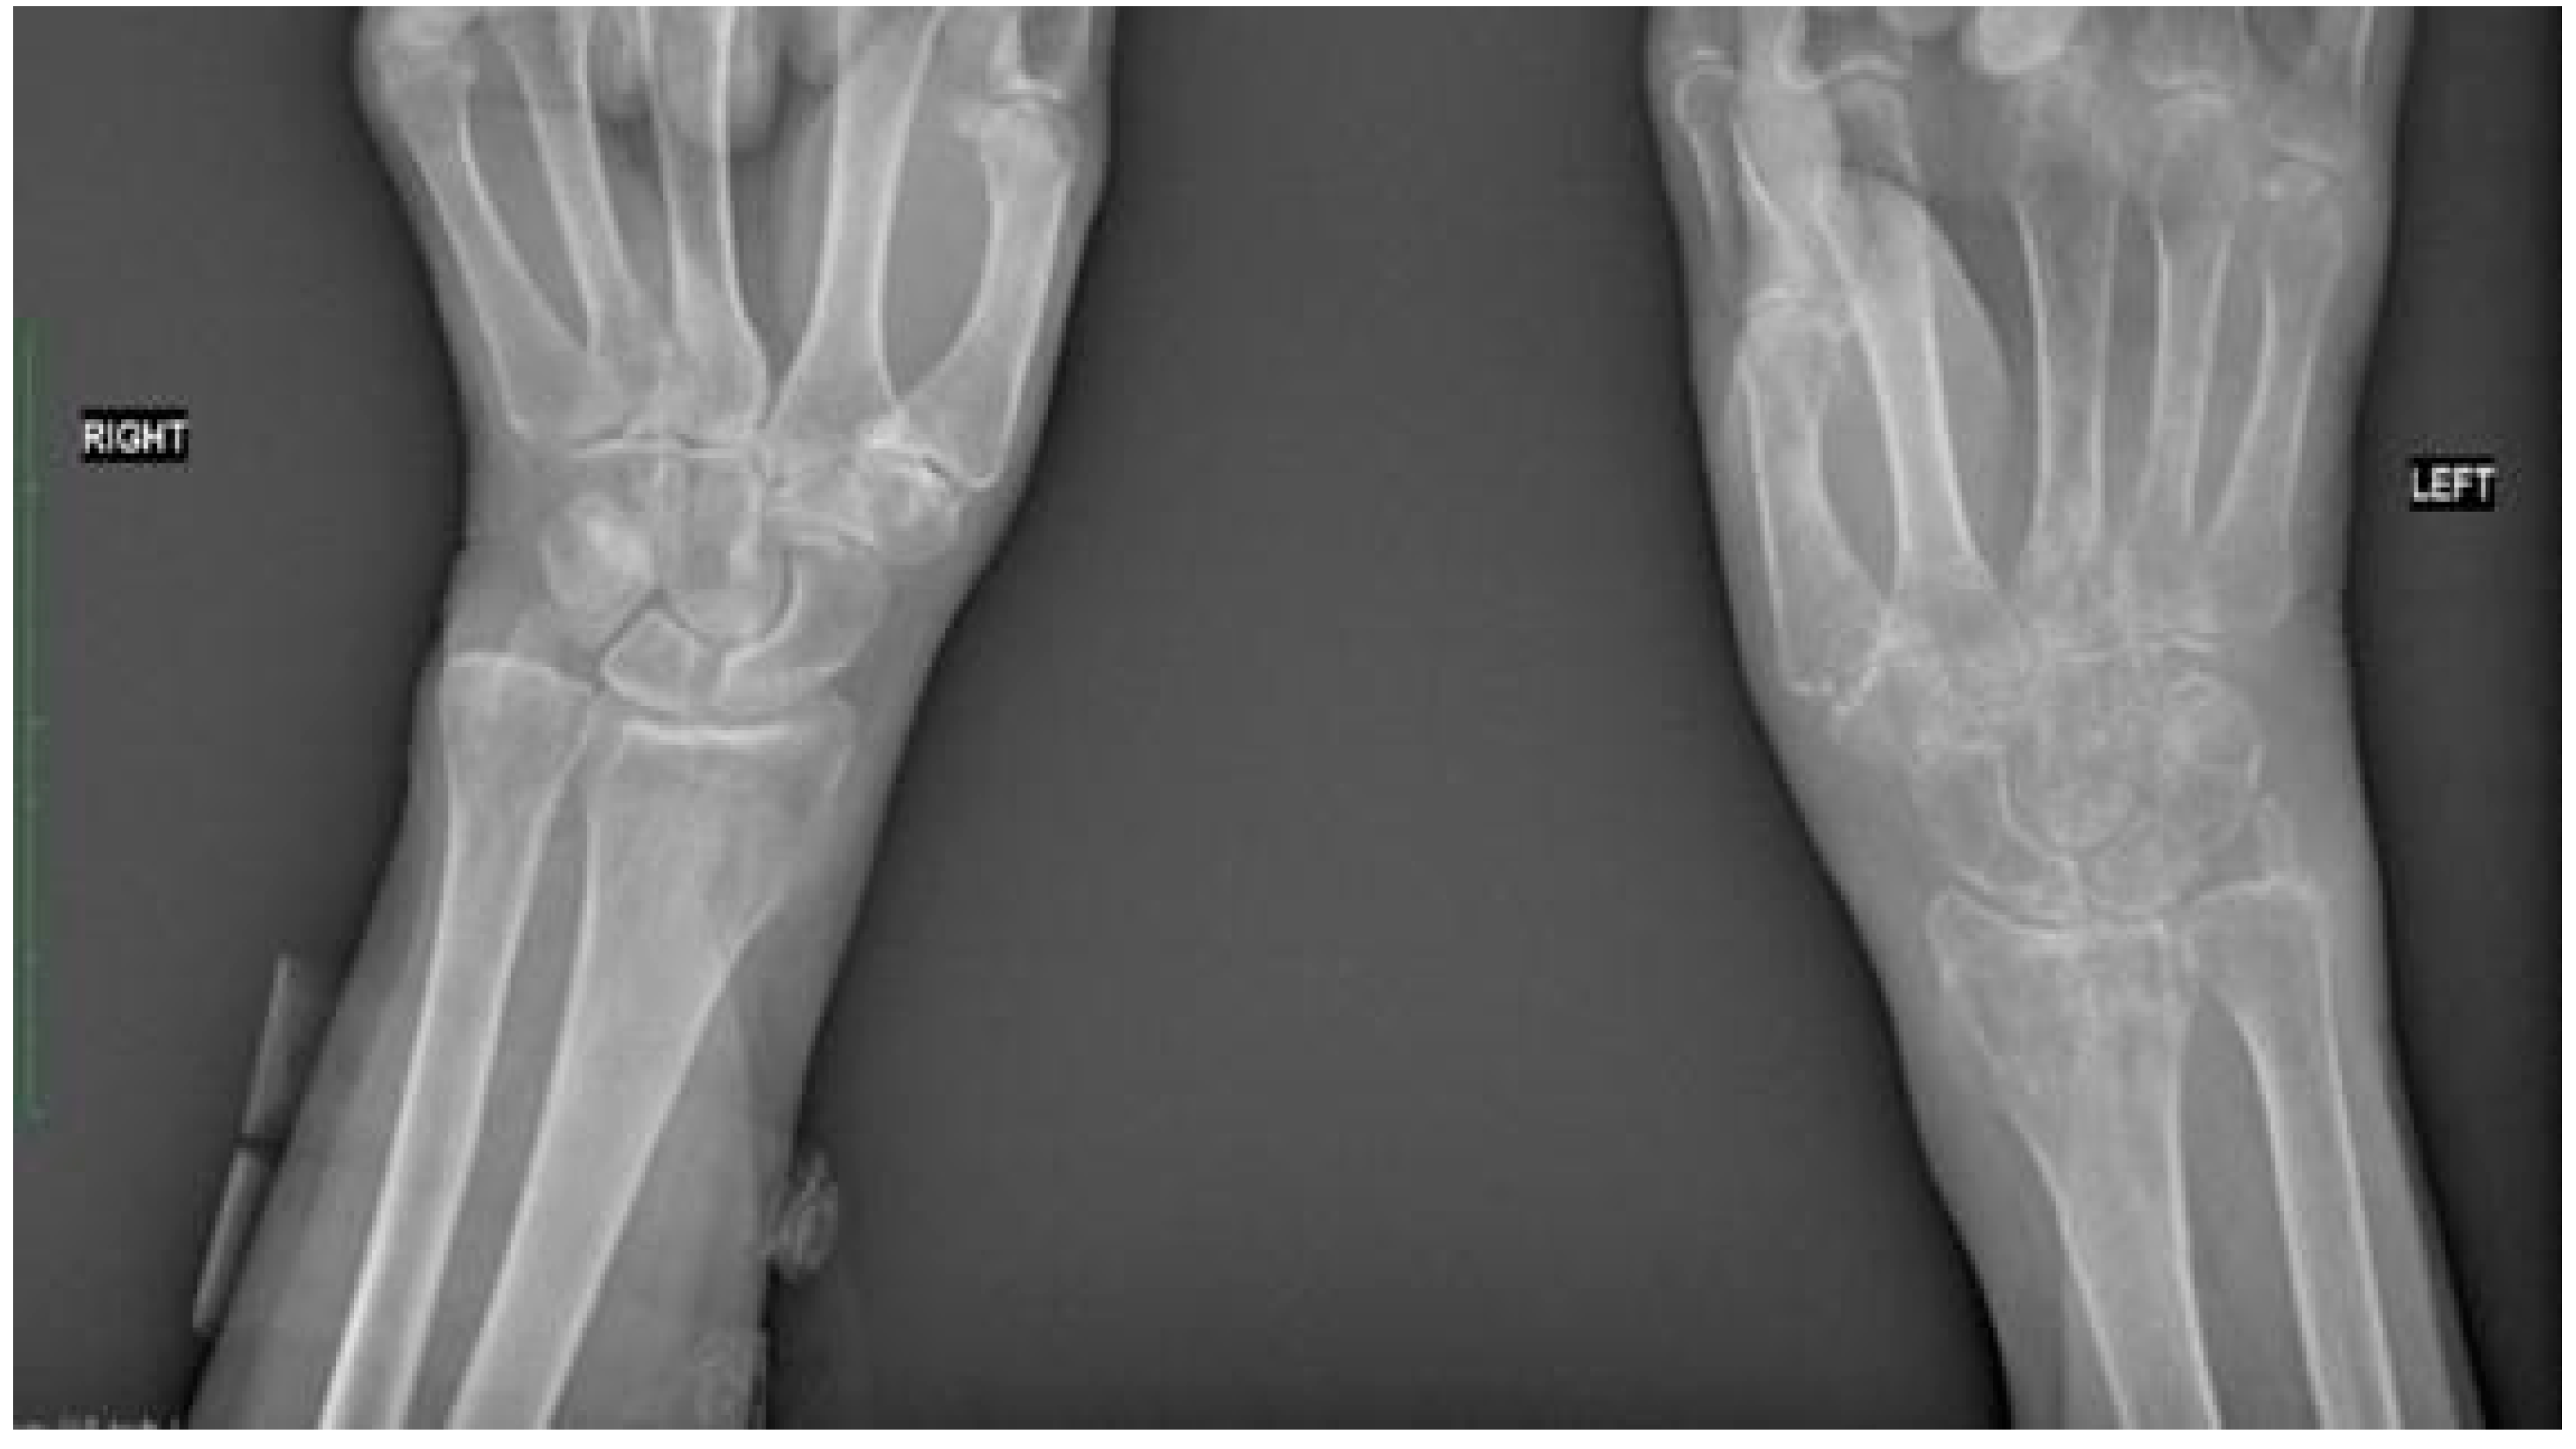

Following admission to the Department of Rehabilitation and Orthopaedics, radiological examination revealed complete fusion of the fracture. However, bone tissue rarefaction in the left upper limb was evident, manifesting as spots affecting the left carpal bones, left radial bone, and the proximal section of the I-V left metacarpal bones (refer to Figure 2). The physical examination of the affected limb indicated severe pain (rated 8/9 on the VAS scale), hyperalgesia, swelling, tightness of the skin, and a glowing appearance The functional capacity of the patient’s hand was significantly impaired, with active movement limited to slight extension of the wrist joint (20°) due to intense pain and edema. The patient was unable to form a fist, and passive movements were also constrained. Specifically, flexion of the left wrist joint, radial and ulnar adduction were 0°, while extension of the wrist joint was partially limited to 60°. Although extension of metacarpophalangeal (MCP) joints, proximal interphalangeal (PIP) joints, and distal interphalangeal (DIP) joints were normal, they were accompanied by severe pain. MCP Joint flexion, abduction, and adduction were limited to 0°, while flexion of the PIP and DIP joints was restricted to 5–10°. Passive supination and pronation were also painfully limited to around 20°. High stiffness in the wrist, MCP, PIP, and DIP joints was observed. Despite significant swelling, no muscle atrophy was noted on the palmar and dorsal surfaces of the left hand or the forearm. The patient scored 0 points in the Frenchay Arm Test (FAT). The remaining joints of the left limb maintained an unaffected range of motion. A comprehensive blood test indicated specific parameter levels: PTH (parathormone): 29.60 pg/mL; calcium: 9.10 mg/dL; 25(OH)D3: 39.4 ng/mL; b-ALP (bone alkaline phosphatase): 4.9 (normal range: 5.3–24.6); CRP (C-reactive protein) <5.0. Based on the Budapest criteria, the patient exhibited at least one symptom from each category (hyperalgesia, skin temperature and color asymmetry, edema, decreased range of motion), leading to the diagnosis of the complex regional pain syndrome (CRPS).

Figure 2.

Comparative radiographic assessment of two wrists in antero-posterior plain shows no bone pathology at the right site. Bone tissue rarefaction is clearly visible on the left side and appears to be like spots. It involves the left carpal bones, the left radial bone, and the proximal part of the I-V left metacarpal bones. There is a loss of joint space between carpal bones and between a distal row of carpal and metacarpal bones.